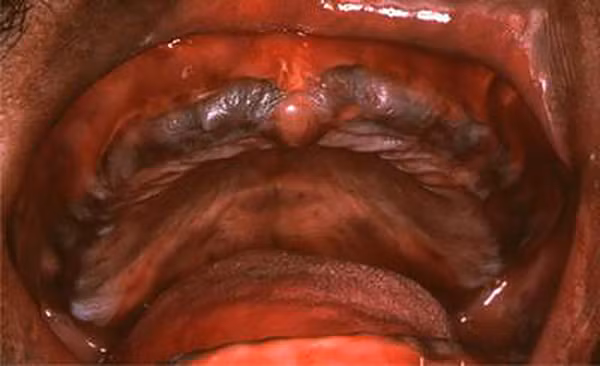

Tuy nhiên, nếu bạn liên tục sử dụng thực phẩm, nguồn nước hay hít vào không khí nhiễm chì trong thời gian dài thì sẽ bị ngộ độc chì nguy hiểm. Ảnh: Sống khỏe.